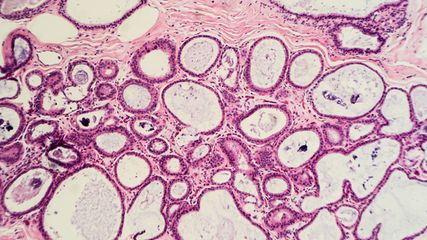

Abb. 2:Das Detailbild zeigt im Zentrum eine drüsenartige Struktur mit zilientragenden Zellen, daneben auch reichlich Schleim. Maßstab 50µm

Der ziliäre papilläre mukonoduläre Tumor der Lunge ist eine neue Entität, der eine charakteristische Morphologie aufweist (Abb. 1–4). Aufgrund der bisherigen Berichte kann von einer geringen Malignität ausgegangen werden. Die molekularen Signaturen lassen aber die Möglichkeit einer Rezidivierung und eventuell sogar einer Metastasierung offen.Dementsprechend kann eine Prognose nicht mit Sicherheit abgegeben werden. Eine engmaschige Kontrolle in den ersten fünf Jahre nach Diagnose ist zu empfehlen.